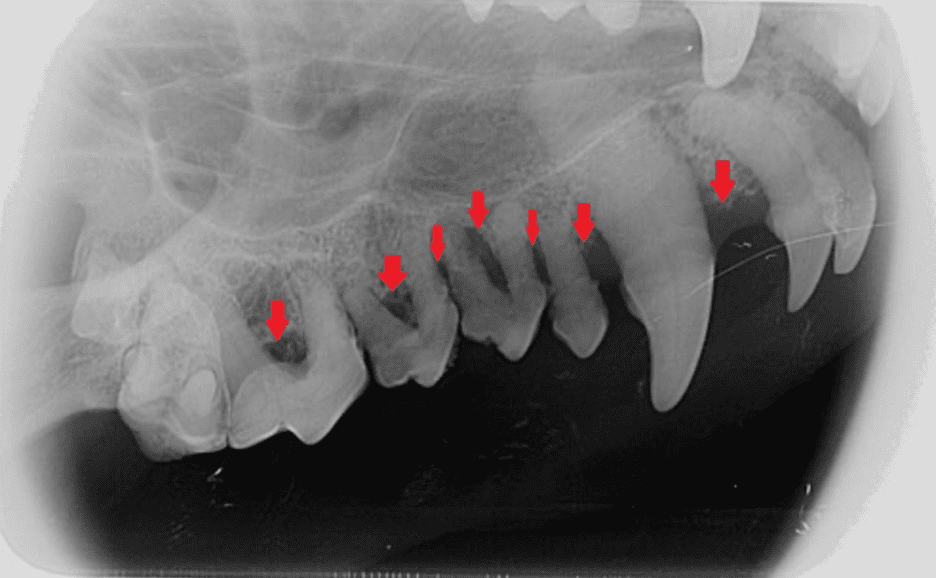

A malocclusion occurs when there is an incorrect alignment between the teeth of the upper and lower jaw, causing a problematic bite. It can manifest in several ways, with the most common types being an overshot bite (Class 2), where the upper jaw protrudes over the lower one; an undershot bite (Class 3), where the lower jaw is extended, and a Class 4 malocclusion, which is a skeletal malocclusion with asymmetry in the front to back, side-to-side, or top to bottom direction. A Class 1 malocclusion is a normal front-to-back relationship of the upper and lower dental arches with one or more individual teeth malpositioned.

Certain breeds, such as Bulldogs, Boxers, and Pugs, are more susceptible to malocclusions due to their brachycephalic (shortened) facial structure. While some malocclusions are purely cosmetic and do not affect the dog’s functionality, others can cause discomfort, difficulty in eating, and risk of periodontal disease due to overcrowding or misalignment of teeth.

Interceptive Orthodontics: This approach involves the early detection and intervention of a developing malocclusion, often in puppies. It includes extraction of deciduous (baby) teeth that may be causing or contributing to a malocclusion, thus allowing the adult teeth to grow in more correctly.

2. Painful occlusal trauma

Tooth Extraction or Reduction: In certain severe cases where other corrective methods are not suitable, extraction or reduction (shortening) of the teeth might be necessary. This method is often used in cases where the malocclusion is causing pain or potential harm to the dog.